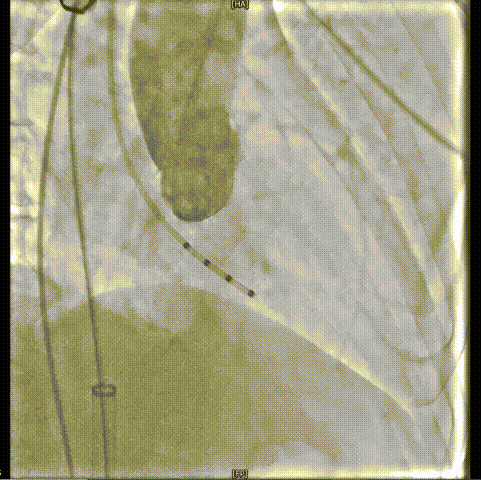

主动脉根部造影

20mm球囊预扩

输送器过弓

瓣膜释放到工作位

23mm瓣膜释放

术后造影